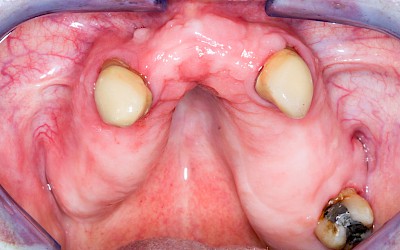

Schwellung ohne Eiter: kugelförmig

Demgegenüber entstehen Auftreibungen der Weichgewebe in Folge mechanischer Dauerreize (Reizfibrom) langsam über Wochen, Monate oder Jahre. Auch Gewohnheiten (Wangensaugen, Lippenbeißen) mit geringem Druck können als Dauerreiz in der Folge zu einer Wucherung der Weichgewebe führen. Fibrome werden nicht selten auch beobachtet in der Nähe einzelner fehlender Zähne – die Lippen oder Wangen beginnen dann, diesen Raum "aufzufüllen" (Vakatwucherung). Reizfibrome sind meist "kugelartig".

Schwellung ohne Eiter: faltenförmig

Als Sonderform des Reizfibroms können bei Zahnprothesen in den Randbereichen selten am Gaumen, häufiger außen in den Umschlagfalten in Ober- und Unterkiefer auch lappenartige Auffaltungen (Lappenfibrome) beobachtet werden, die ebenfalls aufgrund eines mechanischen Dauerreizes entstehen. Alle diese Veränderungen sind in der Regel eher wenig schmerzhaft – auch wenn man darauf drückt. Hier sollte zeitnah mit einem Zahnarzt eine Abklärung erfolgen.